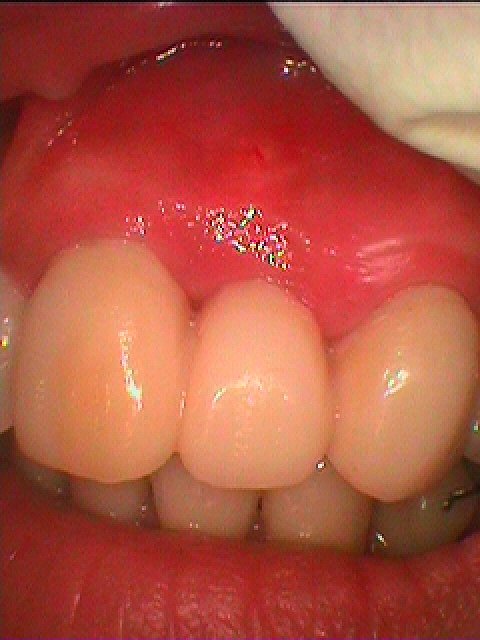

左上2番 根端切除しても治らなく来院 抜歯後ブリッジへ|お知らせ |広島市安佐南区の歯科医院 左上2番 根端切除しても治らなく来院 抜歯後ブリッジへ トップ お知らせ・ブログ お知らせ 左上2番 根端切除しても治らなく来院 抜歯後ブリッジへ 左上2番 根端切除しても治らなく来院 抜歯後ブリッジへ 正面観 問題の歯になります 咬合です 根尖病巣となっていました 抜歯させてもらいましたが、真っ黒です 補填材を入れて縫合して仮歯を入れて終了です ひどく歯茎の下がりも凹みも最小限で済んでいるかと思います 最終補綴は保険のブリッジを入れています Web診療予約 初めての方へ 選ばれ続ける理由 院内設備について 歯が痛いしみる一般歯科 歯がぐらぐらする歯周病 健康な歯を保ちたい予防歯科 子供の虫歯予防をしたい小児歯科 銀歯をセラミックに審美歯科 白い歯を目指しませんか?ホワイトニング 矯正専門医がいるので安心矯正歯科 抜けた歯を補いたいインプラント・入れ歯 医院案内 スタッフ紹介 メリィハウス歯科クリニックオフィシャルホームページ ラベンダー歯科クリニックオフィシャルホームページ お知らせ・ブログ ホーム 診療科目 一般歯科 歯周病治療 予防治療 小児歯科 審美治療 ホワイトニング 矯正歯科 入れ歯・インプラント マウスピース矯正 初めての方へ 院長・スタッフ 設備紹介 医院案内・アクセス メニューを閉じる